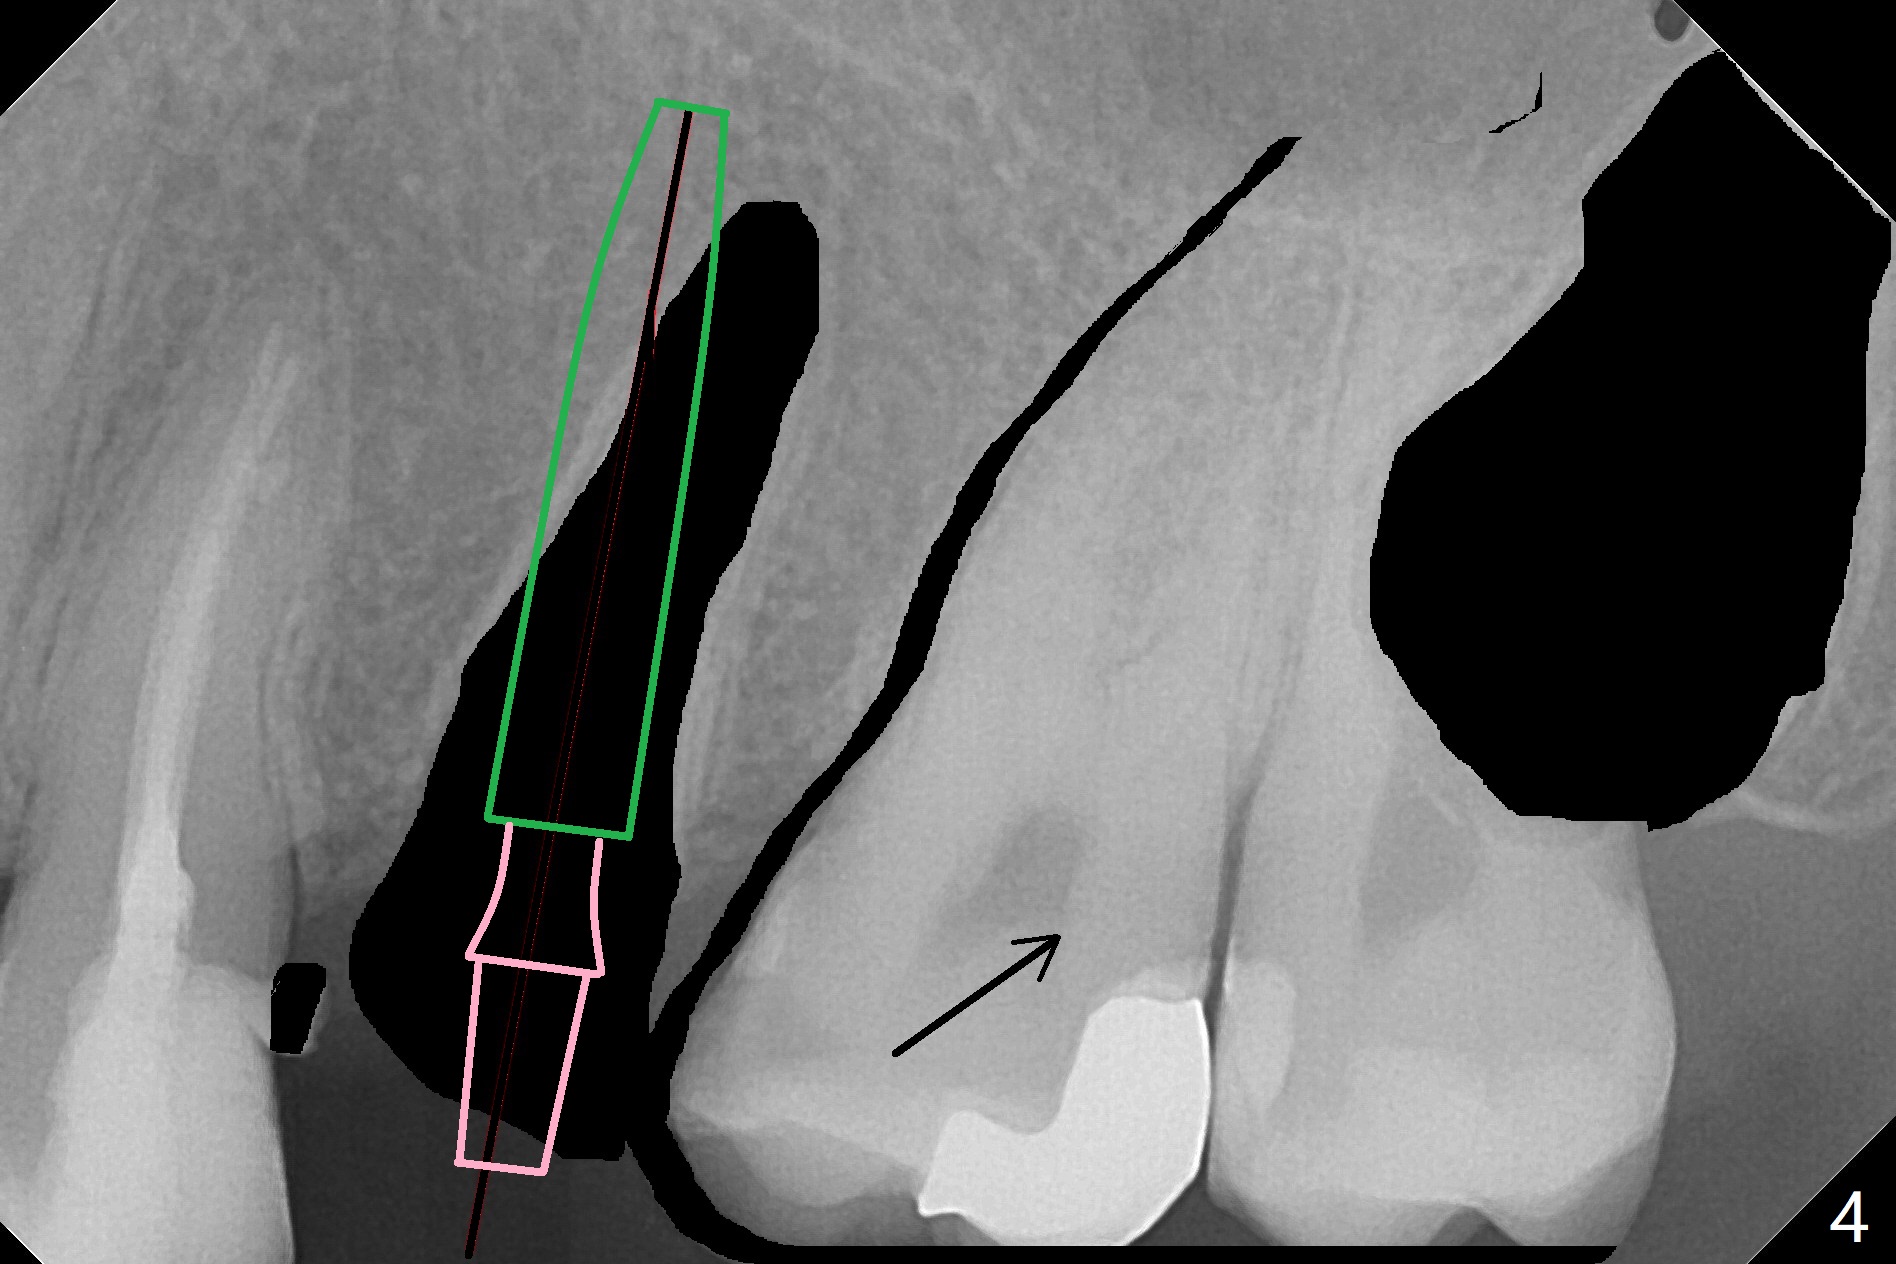

A 27-year-old man returns to clinic with #13 subgingival fracture, which is associated with Class III malocclusion and anterior open bite (Fig.1). Both #1 and 16 seem to be buccal to the 2nd molars, causing root resorption (Fig.1 *). Since the root of the 2nd premolar tilts distal, osteotomy for an implant will be in the mesiopalatal aspect of the extraction socket (Fig.2,3 red). Following implant placement, #16 will be extracted (Fig.3 black), laying foundation to distalize and intrude #14 and 15 to make space for #13 implant crown and reduce anterior open bite and posterior tooth overloading (Fig.4 arrow). No Deviation Clindamycin Xin Wei, DDS, PhD, MS 1st edition 08/25/2020, last revision 09/08/2020